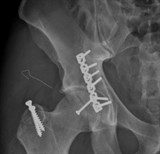

Phẫu thuật thành công cho phi công Canada gãy trật khớp háng nặng

TĐO - Chỉ sau 3 ngày mổ cấp cứu gẫy trật khớp háng nặng do tai nạn giao thông, anh Dustin Spencer (34 tuổi, người Canada) đã có thể bắt đầu tập đi lại. Với một người là phi công thủy phi cơ, sức khỏe là yếu tố sống còn như anh Dustin thì sự hồi phục nhanh chóng phẫu thuật sau ca mổ tại Bệnh viện Đa khoa Quốc tế Vinmec Times City khiến anh rất bất ngờ và hài lòng.